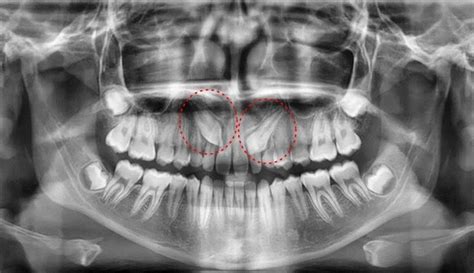

Diagnóstico del Canino Incluido

En la exploración clínica, el signo más visible de que el colmillo presenta un problema de erupción es su ausencia en la boca, una vez transcurrido el plazo en el que debe salir. Adicionalmente, el odontólogo puede identificar otras señales durante la exploración oral, como la persistencia del canino de leche en la boca más allá de la edad recomendada. Por otro lado, el colmillo incluido puede sentirse a la palpación.

En lo que respecta a la exploración radiológica, será necesario realizar una radiografía panorámica y un TAC dental. De esa manera, el dentista podrá observar cuál es la situación del colmillo en la boca (posición, altura, inclinación…) así como su relación con los dientes vecinos.